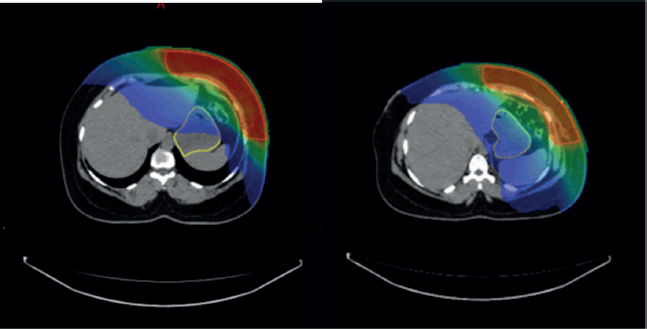

Overall, the significant factors influencing acute upper GI toxicity included radiation technique, RT dose and dose to stomach (D10 cc, D30 cc and D60 cc). Importantly, left chest wall or breast irradiation with or without RNI during FB was associated with a significantly higher risk of GI toxicity compared to DIBH, which holds a significant negative correlation implying a protective effect and helps in reducing GI toxicity (p = 0.035) (Supplementary

Figures 1a,b and 2a,b). Additionally, a positive correlation was found between larger PTV volume and the risk of developing acute upper GI toxicity (p = 0.036).

The Mann-Whitney U test was used to compare stomach dose parameters (D10, D30 and D60 cc) between FB and DIBH. Stomach D10 cc, the higher-dose region most closely associated with acute toxicity, showed no significant difference between FB and DIBH (Mann-Whitney U = 898.500, Z = −1.712, p = 0.087). This suggests that DIBH helps control the dose to critical stomach sub-volumes, potentially reducing the risk of upper GI toxicity. Interestingly, D30 and D60 cc doses were higher in the DIBH group (p = 0.013 and p = 0.002, respectively). However, these differences are likely to reflect anatomical and positional variations associated with breath-hold techniques rather than an increased clinical risk. Clinical correlation with upper GI toxicity indicated a protective trend for DIBH, reinforcing its role in mitigating toxicity by improving treatment reproducibility and reducing motion-related dose variability (Supplementary Figure 2a and b).

Supplementary Figure 1. (a and b): Axial CT scan showing stomach position in FB (VMAT Technique), Figure 3b: showing stomach position in DIBH (VMAT Technique).

Supplementary Figure 2. (a): Coronal view showing stomach position in FB (VMAT), (b): In DIBH (VMAT).